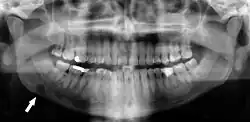

Panoramic radiograph showing Stafne defect (arrowed).